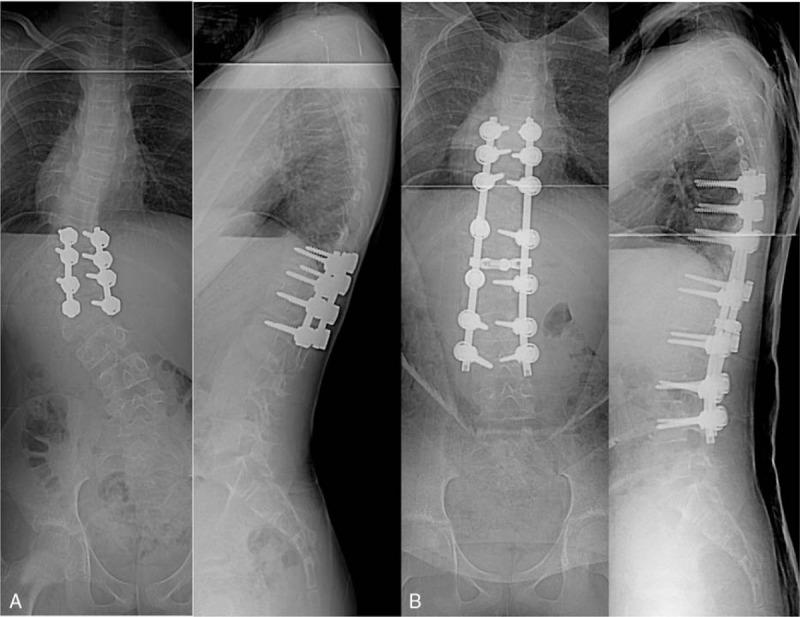

We report an 11-year follow-up of revision surgery for fractional curve progression after combined anterior and posterior fusion without hemivertebra resection using pedicle screw fixation (PSF) in congenital kyphoscoliosis at age 4 years (a total 18-year follow-up). A T12 hemivertebra was documented in a 4-year-old girl and was treated by combined anterior and posterior fusion in two stages with PSF. The fusion mass was maintained but the distal compensatory curve progressed during the follow-up period. The patient underwent a posterior vertebral column resection (PVCR) with extended posterior fusion at the age of 11, 7 years after initial surgery.

Eleven years after the revision surgery with PVCR, the patient showed satisfactory results and her spine was well balanced.

我们报告了一例4岁先天性脊柱后凸侧凸患者在未行半椎体切除的情况下采用椎弓根螺钉固定(PSF)进行前后联合融合术后因分节段曲线进展而进行翻修手术的11年随访情况(总计18年随访)。一名4岁女孩被诊断为T12半椎体,分两阶段采用PSF进行前后联合融合治疗。随访期间融合块保持稳定,但远端代偿性曲线进展。患者在初次手术后7年,即11岁时接受了后路脊柱椎体切除术(PVCR)及扩大后路融合术。

PVCR翻修手术后11年,患者效果满意,脊柱平衡良好。